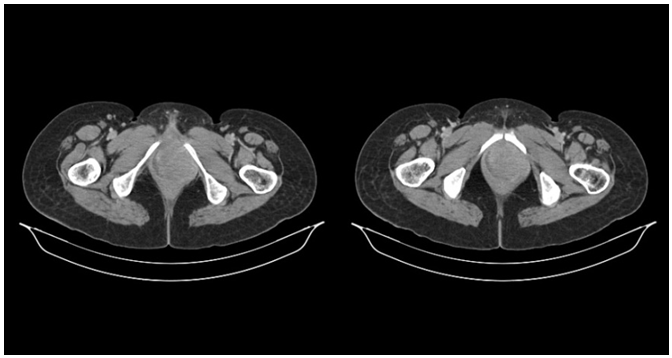

Figure 1A & 1B lesion with internal necrotic area involving vagina more on left side extending upto labial fold.

Rectal examination- B/L paravaginal medially involved rectal mucosa free. Routine haemogram, liver and renal functions are within normal. Chest radiograph revealed no abnormality and contrast-enhanced computed tomography (CECT) thorax revealed few calcified nodes in right hilar region and sub-carinal region sized nodule with bilateral lung metastasis and liver metastasis, heart, great vessels, bilateral bronchi were normal. CECT abdomen revealed liver metastasis both right and left kidneys normal other organs and biliary tree were normal; no abdominal lymphadenopathy was evident. Pelvic CECT scan showed a 57*47*120mm lesion with internal necrotic area involving vagina more on left side extending upto labial fold, both ischiorectal fossa, infiltrates proximal part of left obturatus internus, loss of fat plane with rectum and anal canal, 40*38mm fibroid involving fundus of uterus, Bilateral adnexa were normal with no ascites or lymphadenopathy. Bone scan is normal. Punch biopsy of the vaginal mass was then performed which showed poorly differentiated adenocarcinoma with probable neuroendocrine differentiation. Immunohistochemistry was done with a panel of antibodies, which revealed Ewing’s sarcoma. Following our diagnosis of primary Ewing’s sarcoma or PNET of the vagina, our patient was subjected to combination chemotherapy for 35days 1 cycle VACA, during chemotherapy disease was progressive, then patient was send for palliative radiotherapy 30Gy/15# (200CGy/# ) by AP/PA portal, during which our patient was found to be clinically progressive disease. Following this she was on palliative chemotherapy, single agent (Adriyamycin) (Table 1).